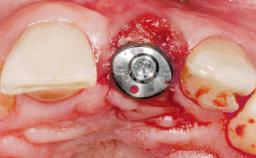

This 43-year-old male patient, a non-smoker, came to our practice because of a fracture of tooth 12 caused by a bicycle accident. Due to the combined para- and infrabony crown and root fracture, tooth extraction, and subsequent implant placement were suggested to the patient as the therapy of choice. The patient had high esthetic expectations with regard to the treatment outcome and asked for an immediate fixed provisional restoration. His individual esthetic risk profile summed up to a medium esthetic risk.

Placement Protocol Immediate implant placement

Tooth Site Maxillary incisor or canine

Socket Morphology Single-root socket

Socket Integrity Sufficient, with intact bone walls

Bone Volume Sufficient, with intact walls